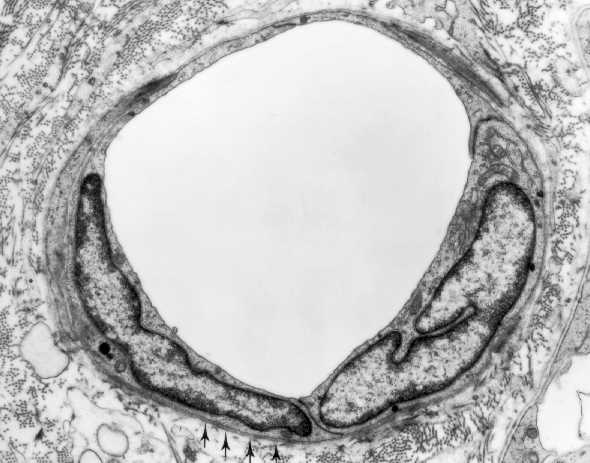

Simple squamous epithelium(endothelium) lining the lumen of a blood capillary. Could you recognize the cell junctions between the two cells? What do the arrows indicate?